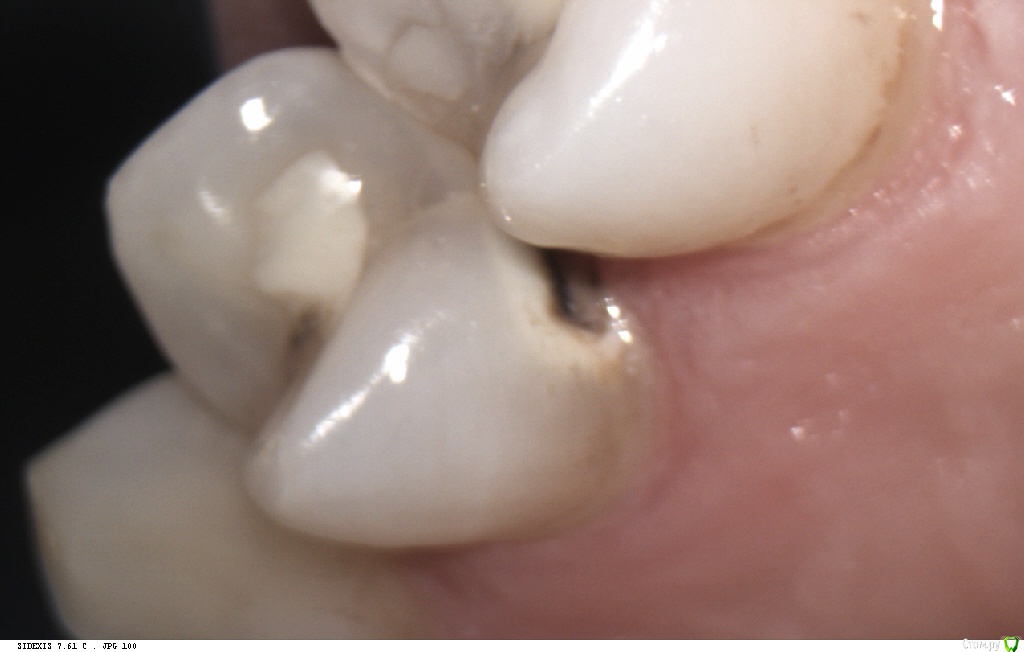

Pan Опубликовано 6 мая, 2017 Поделиться Опубликовано 6 мая, 2017 (изменено) типичная локализация кариеса при плохой гигиене и злоупотреблении в питании фастфуда. Ну понятно, что всё это на фоне сниженной кариесрезистентности. Первым делом нужно объяснить девушке значимую роль питания и гигиены в развитии кариозных процессов. Изменено 6 мая, 2017 пользователем Pan 1 Ссылка на комментарий

Л Ю С Я Опубликовано 9 мая, 2017 Поделиться Опубликовано 9 мая, 2017 Прям Фауст фуд во всем и виноват))) и гигиена по фото не такая уж плохая. Зубные отложения, конечно, присутствуют. Но гингивита, характерного для регулярно неудовлетворительной гигиены нет. У меня есть пациентка, тоже около 30, очень сознательная, со здоровьем и образом жизни все в порядке, регулярно использует флосс, щётка электрическая. Там кпу 26-28. Удаленных зубов нет, за счёт регулярного посещения стоматолога. Депульпированных 4-5. Ходила раз в 3 месяца , стабилизировали процесс за счёт профессиональной гигиены, антибактериальными ополаскивателями, туфмусс и фторированием. Исчезла на 1 год, случилась беременность и роды. Явилась через 2 месяца после родов. Гигиена отличная, Фауст фуд не ест)), зато кариес съел практически все целые контакты и шейки. Мотивируем на Тотал 1 Ссылка на комментарий

Pan Опубликовано 11 мая, 2017 Поделиться Опубликовано 11 мая, 2017 (изменено) Деструкция эмали (в типичных для зубного налета местах) произошла значительно ранее ( разве нужно еще раз говорить об истинных причинах, способствующих этому процессу?) Потом, конечно, индивидуум (взрослея) изо всех сил старается и отсутствие признаков гингивита(если хотите) тому подтверждение. Но, увы, процесс уже запущен... Вы конечно же не хотите оспорить тот факт, что деструкцию эмали (кариес) вызывают бактерии зубного налета. Изменено 11 мая, 2017 пользователем Pan Ссылка на комментарий